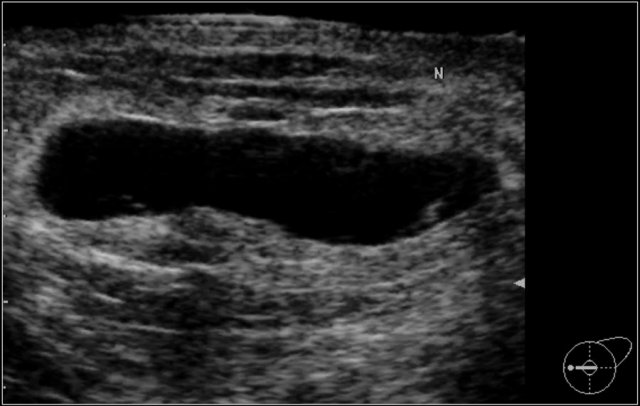

BI-RADS Category 2: Mass seen on mammogram proved to be a cyst. BI-RADS Category 2: Mass seen on mammogram proved to be a cyst.

Additional US of the mass: Concordant with the lump and the mass on the mammogram there is an oval simple cyst, parallel orientation, circumscribed, Anechoic with posterior enhancement. Size : 3,5 x 1,5 cm.

In the right breast at least 2 more smaller cysts.

BI-RADS 2 (benign finding).

The palpable mass is a simple cyst. There are at least two more, smaller cysts present in the right breast.